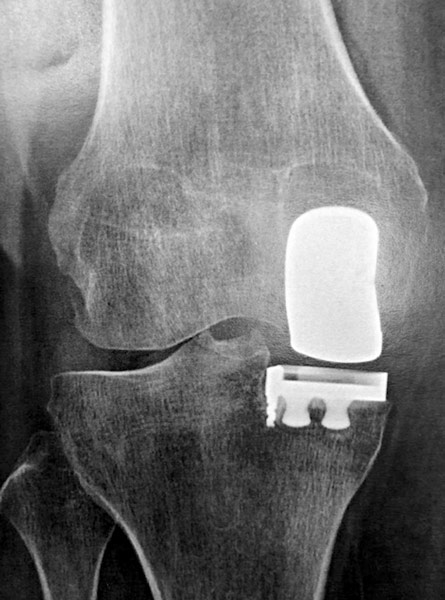

Homme 60 ans, opéré par prothèse rotulienne et prothèse uni-compartimentale interne. Toujours douloureux.

Pas d’infection.

Changement pour mettre en place une prothèse totale du genou. Aucune douleur résiduelle.